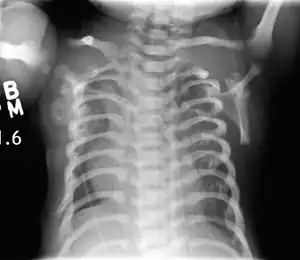

| CXR of a newborn with asphyxiating thoracic dysplasia. Note the short ribs. | |

This diagnosis is grouped with other chest problems called thoracic insufficiency syndrome (TIS). Diagnosis of Jeune syndrome can be made as early as before birth if signs and symptoms are apparent on an ultrasound; however, diagnosis after birth usually occurs through X-rays and genetic testing, such as the tests found on the Genetic Testing Registry Archived 2021-03-18 at the Wayback Machine (GTR).[9]